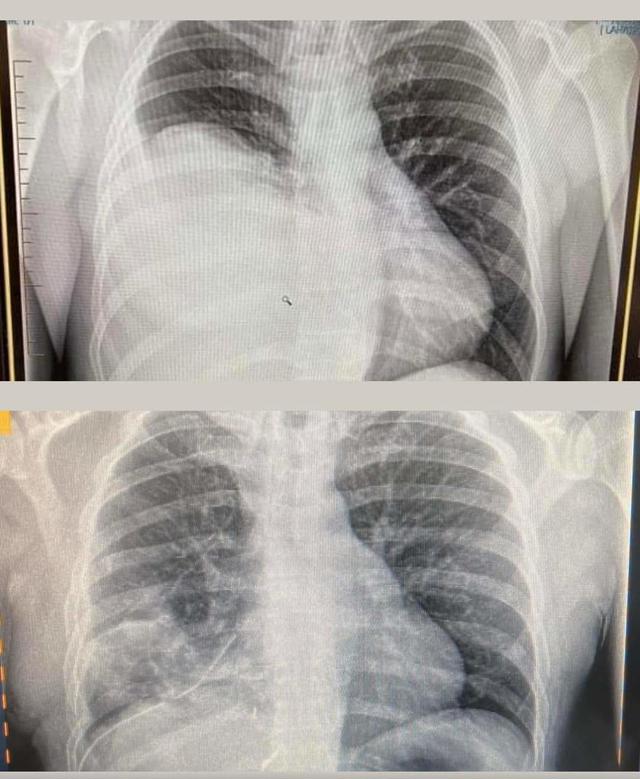

You don’t need to be a medical professional to see the difference between the very first X-ray (top) that picked up Hamish’s tumour back in August, and then the one under, around a week post op. Bloody scary I can tell you to see that for the first time 😱

By the time Hamish got to surgery, it had grown again and his right lung was completely sandwiched and non functional, and his heart had shifted and was severely compressed, more than what anyone had realised. He was lucky not to have had a cardiac event or stroke, and the specialists were blown away that he had been functioning as well as what he had.